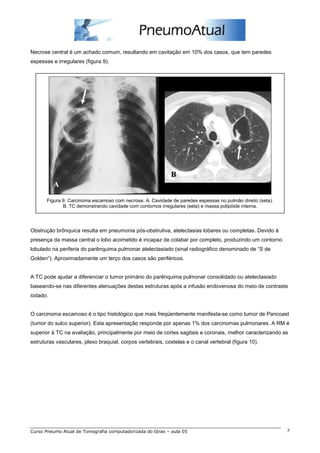

Necrose central é um achado comum, resultando em cavitação em 10% dos casos, que tem paredes

espessas e irregulares (figura 9).

Figura 9. Carcinoma escamoso com necrose. A. Cavidade de paredes espessas no pulmão direito (seta).

B. TC demonstrando cavidade com contornos irregulares (seta) e massa polipóide interna.

Obstrução brônquica resulta em pneumonia pós-obstrutiva, atelectasias lobares ou completas. Devido à

presença da massa central o lobo acometido é incapaz de colabar por completo, produzindo um contorno

lobulado na periferia do parênquima pulmonar atelectasiado (sinal radiográfico denominado de “S de

Golden“). Aproximadamente um terço dos casos são periféricos.